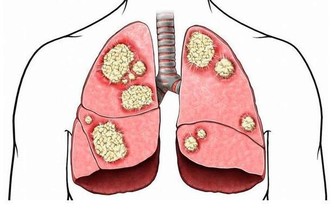

*****3.置換類的手術*****

有時需要換肝這種高難度的手術,手術過程複雜多樣,

在做這種手術時,對於病人來說需要開胸,自己衣服上可能攜帶一些病菌,在手術過程中造成不必要的影響,